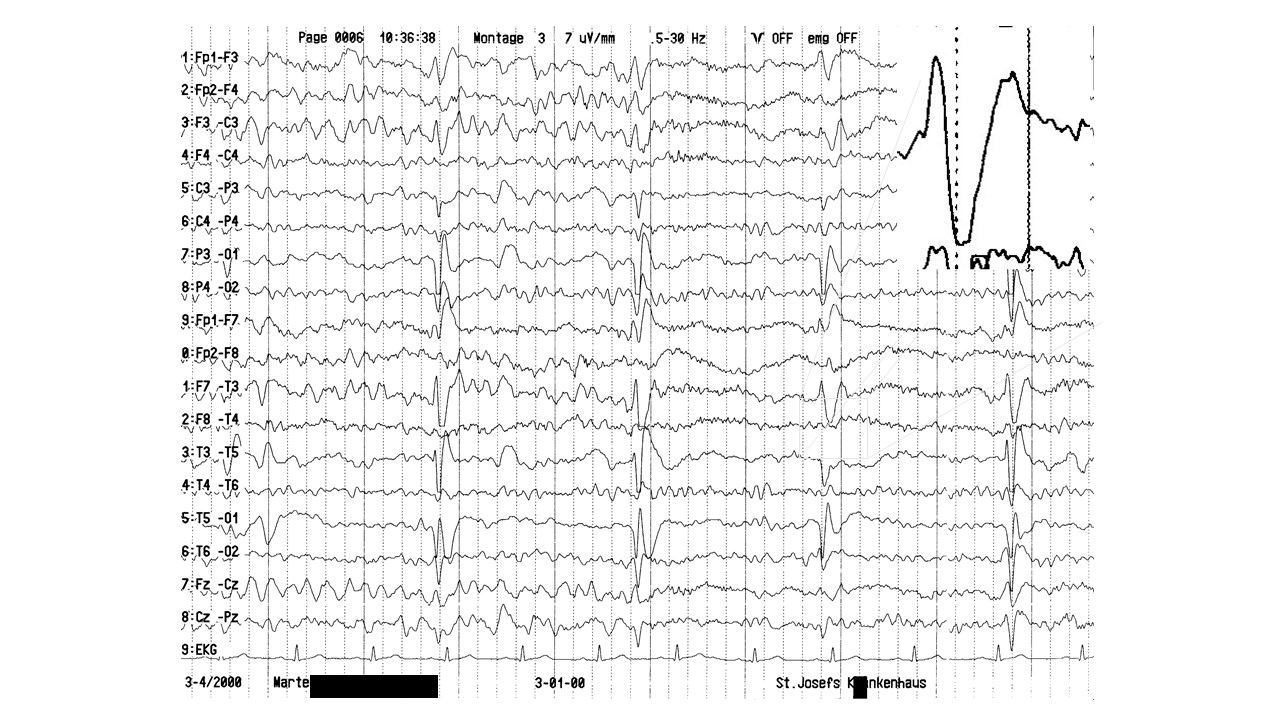

EEG-Seminar I | 43.45 zurück | weiter

folie607.jpg